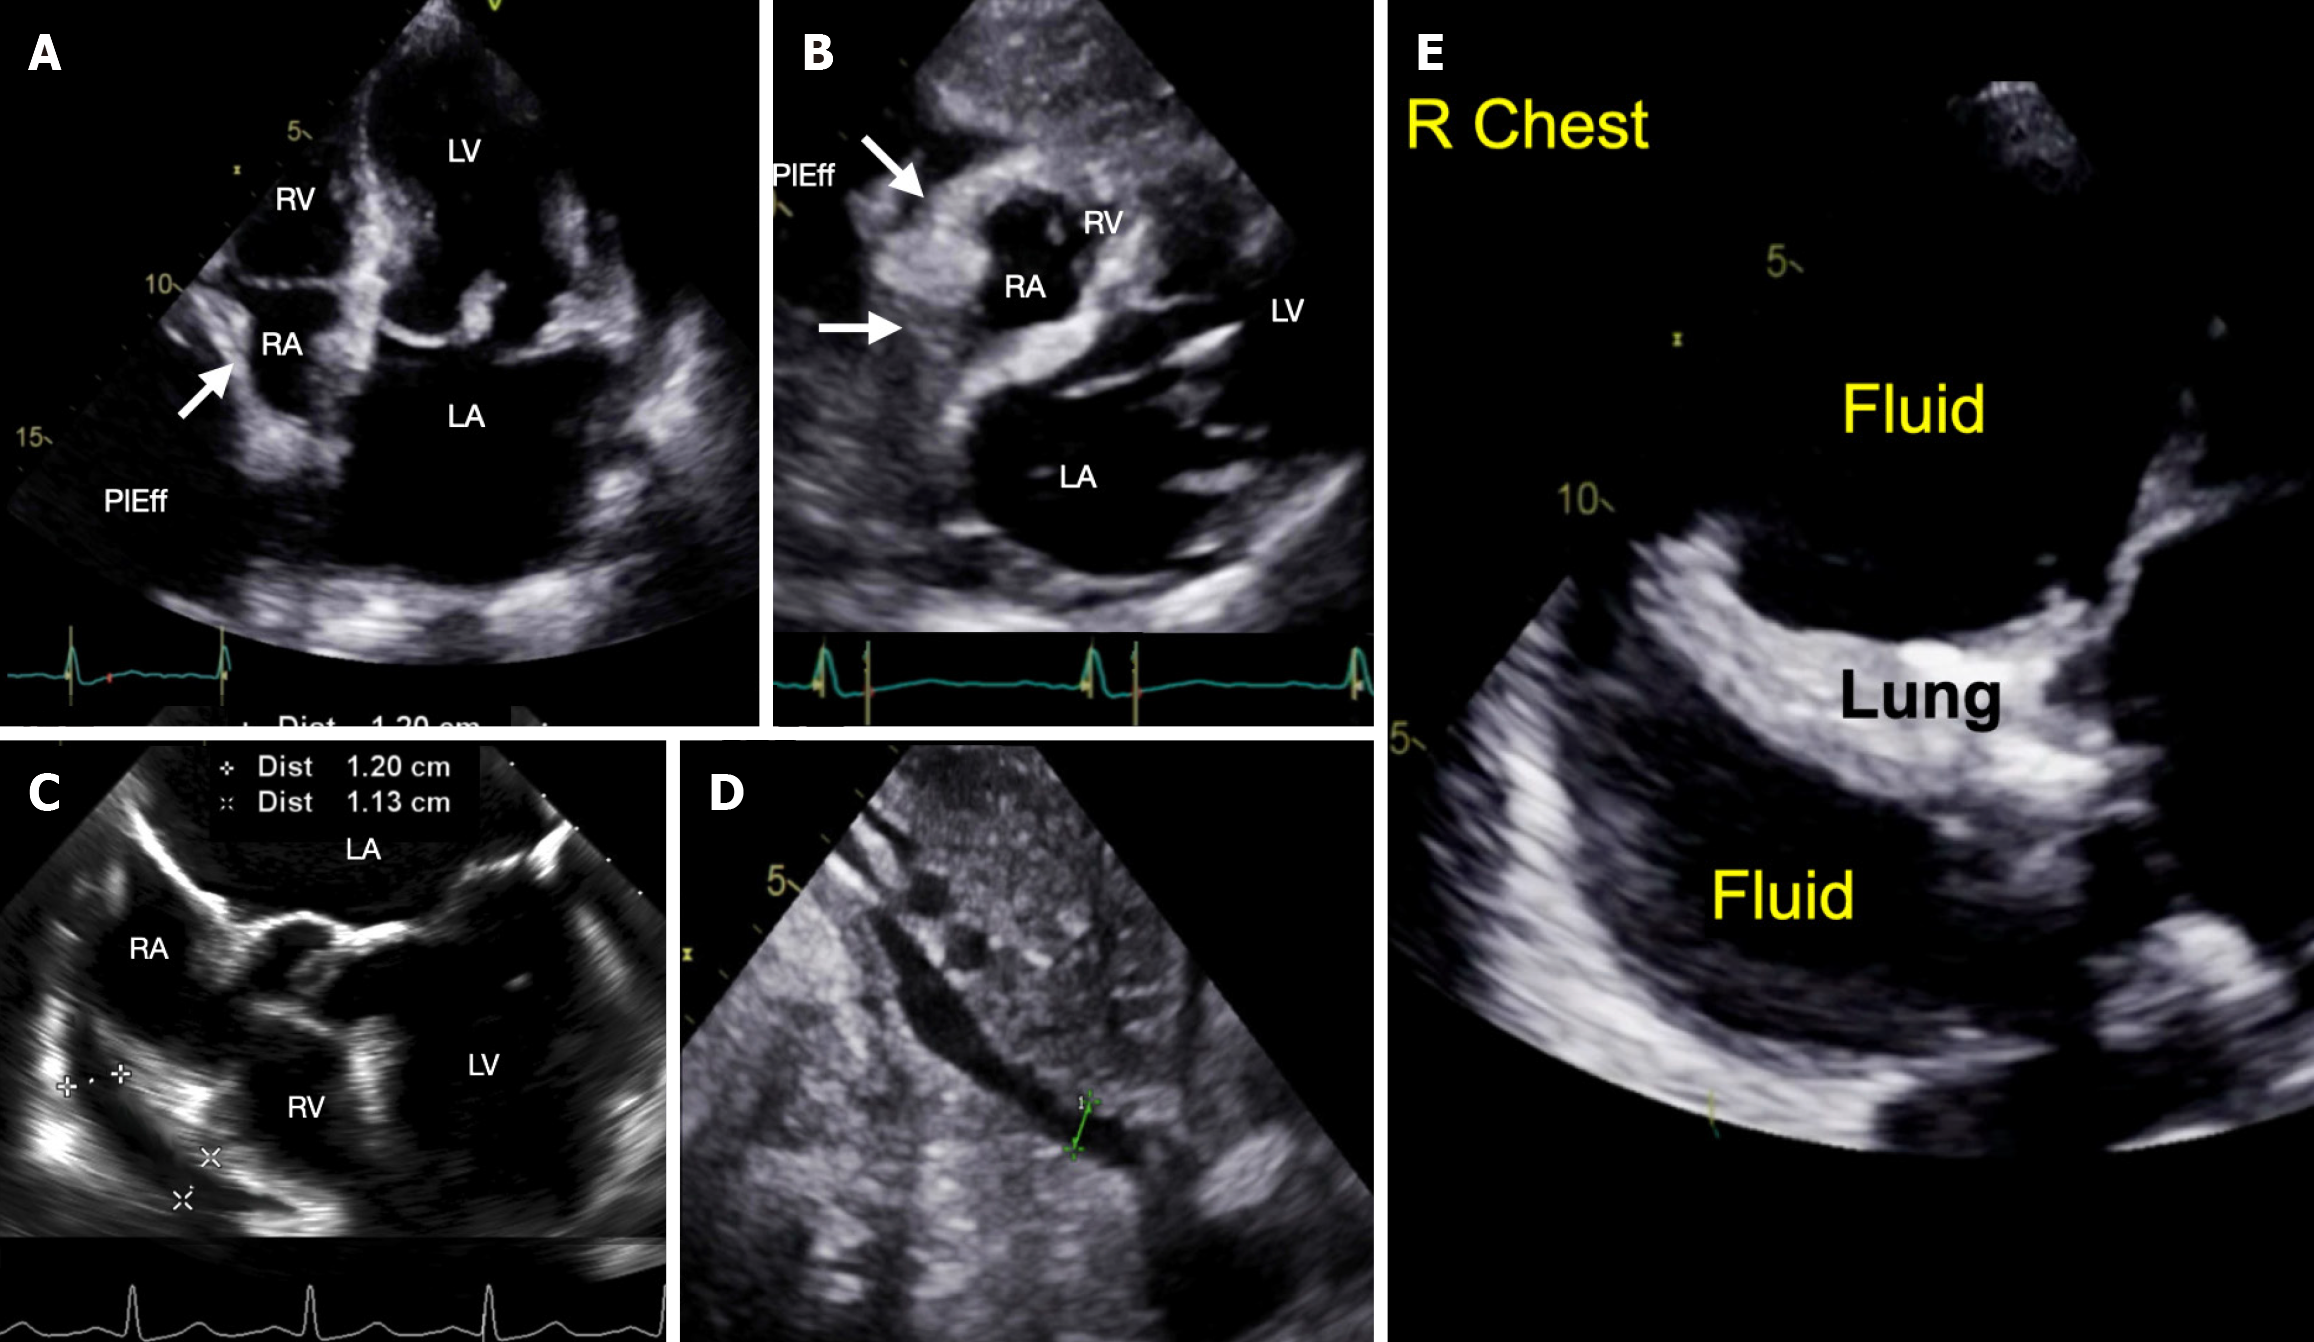

Figure 1 Point-of-care ultrasound exam.

A: Post-procedure cardiac apical four-chamber view showing large fluid collection posterior and lateral (PlEff) to the right atrium (RA) causing RA collapse (white arrow showing inward position of the RA wall) during ventricular systole (i.e., atrial diastole); B: Post-procedure cardiac subcostal view showing four chambers and RA collapse during atrial diastole (white arrows showing inward position of the RA wall) and a small right ventricle (RV); C: Transesophageal echocardiographic view, obtained during the procedure, showing pericardial effusion along the RA and right ventricular chambers (RV) measuring approximately 1.1 to 1.2 cm; D: Post-procedure subcostal view showing inferior cava diameter of 0.8 cm; E: Ultrasound of the right chest demonstrating collapsed lung and a large right chest fluid.